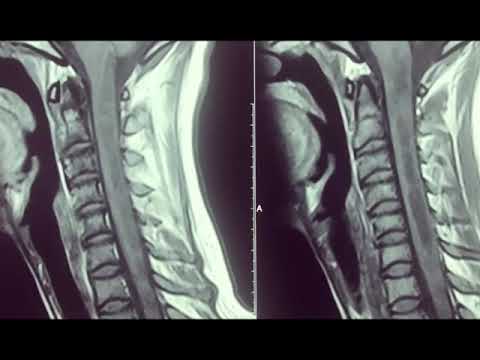

Hellow guys, Welcome to my website, and you are watching Cervicomedullary brainstem tumor resection. and this vIdeo is uploaded by Pediatric Neurosurgical Techniques at 2023-12-22T15:34:43-08:00. We are pramote this video only for entertainment and educational perpose only. So, I hop you like our website.